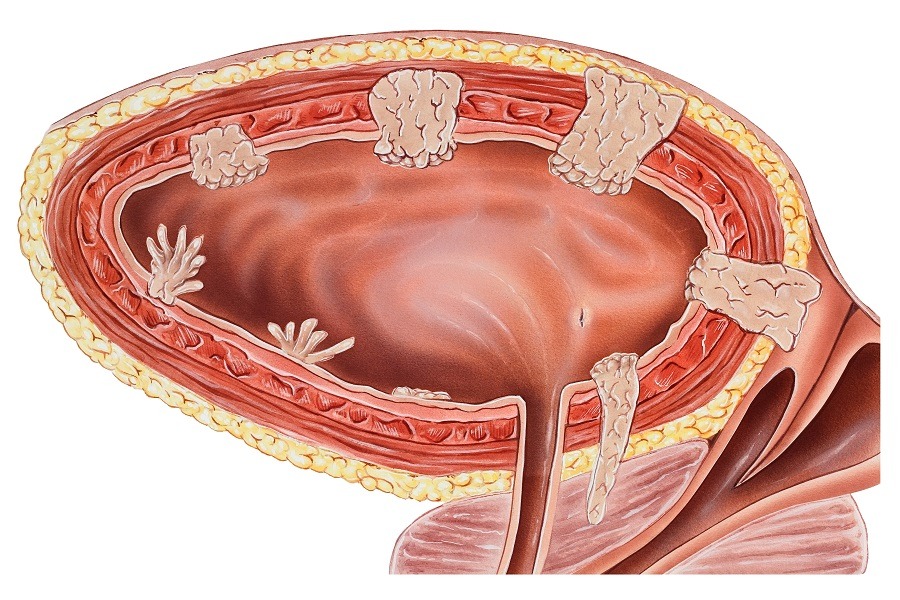

Cancer de la vessie

Résection, laser, instillations intravésicales de BCG, cystectomie totale avec création d’une néo-vessie intestinale.